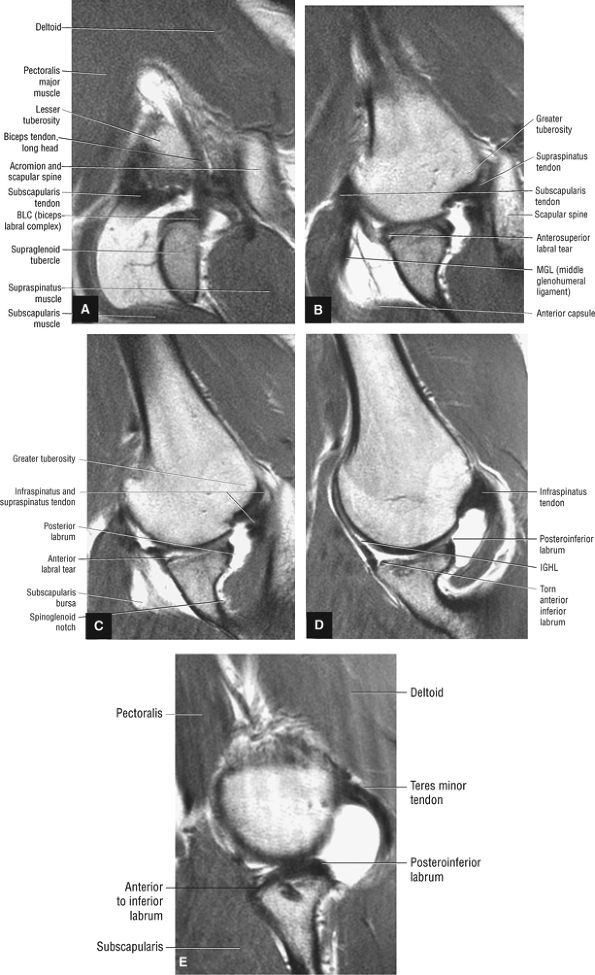

FIGURE 8.9 ● ABER MR arthrogram showing sequential images from superior to inferior. (A) Superior axial oblique image at the level of the biceps labral complex and the long head of the biceps tendon. (B) Anterosuperior axial oblique image at the level of the subscapularis tendon and supraspinatus footprint. (C) Mid-axial oblique image at the level of the conjoined insertion of the supraspinatus and infraspinatus tendons and the spinoglenoid notch. (D) Anteroinferior axial oblique image at he level of the IGL and infraspinatus tendon. (E) Inferior axial oblique image at the level of the inferior labrum and teres minor tendon.